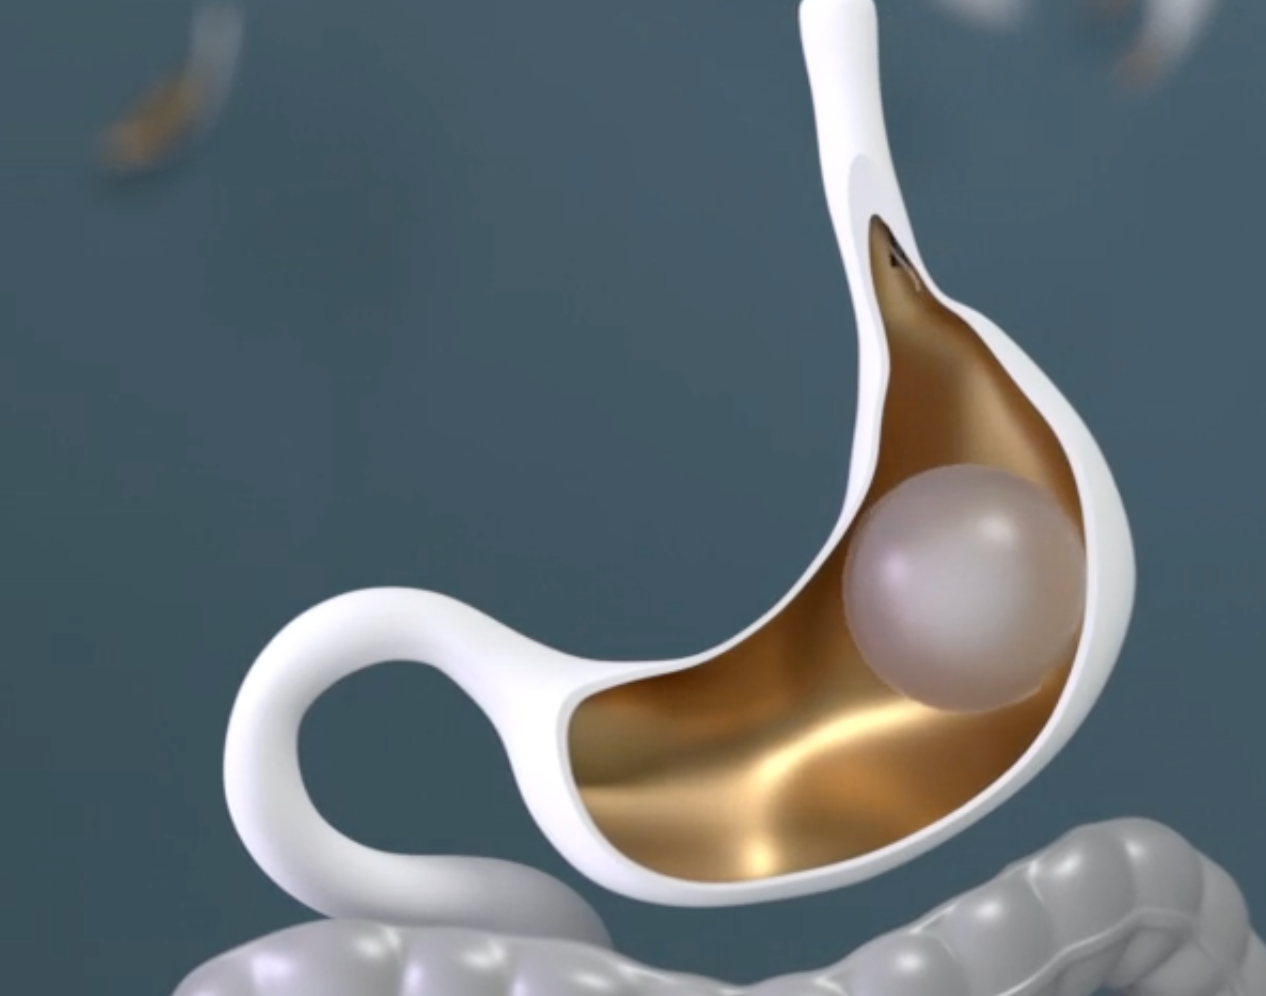

Compare 5 common gastric balloon types, how they work, and which one may be best for your weight loss goals. Learn what to expect and how to choose wisely.

Wondering what to expect before and after gastric balloon? Learn all about non-surgical gastric balloon, from how it works to typical weight loss results.

Wondering about 6-month gastric balloon results? Learn what to expect and find out how this non-invasive approach can kickstart your weight loss goals!

Discover the proven effectiveness of the gastric balloon procedure for weight loss and how it can jumpstart your journey towards a healthier lifestyle.

Learn more about the benefits of ESG and gastric balloon, two endoscopic procedures that can help you achieve your goals.